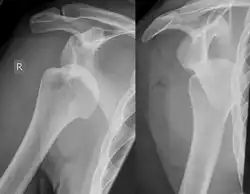

Hill–Sachs lesion post-shoulder dislocation

X-ray at left shows anterior dislocation in a young man after trying to get up from his bed. X-ray at right shows same shoulder after reduction and internal rotation, revealing both a Bankart lesion and a Hill-Sachs lesion.

Diagnosis can be suspected by history and physical examination which is usually followed by imaging. Because of the mechanism of injury, apprehension of anterior dislocation is common with provocative maneuvers. Hill–Sachs lesions have been classified as "engaging" or "non-engaging", with engaging lesions defined by the ability of the glenoid to sublux into the humeral head defect during abduction and external rotation. Engaging dislocations have a higher risk of recurrent anterior dislocation, and their presence can help guide surgical management.[2] Imaging diagnosis conventionally begins with plain film radiography. Generally, anteroposterior (AP) radiographs of the shoulder with the arm in internal rotation offer the best yield while axillary views and AP radiographs with external rotation tend to obscure the defect. However, pain and tenderness in the injured joint make appropriate positioning difficult and in a recent study of plain film x-ray for Hill–Sachs lesions, the sensitivity was only about 20%. i.e. the finding was not visible on plain film x-ray about 80% of the time.[3]